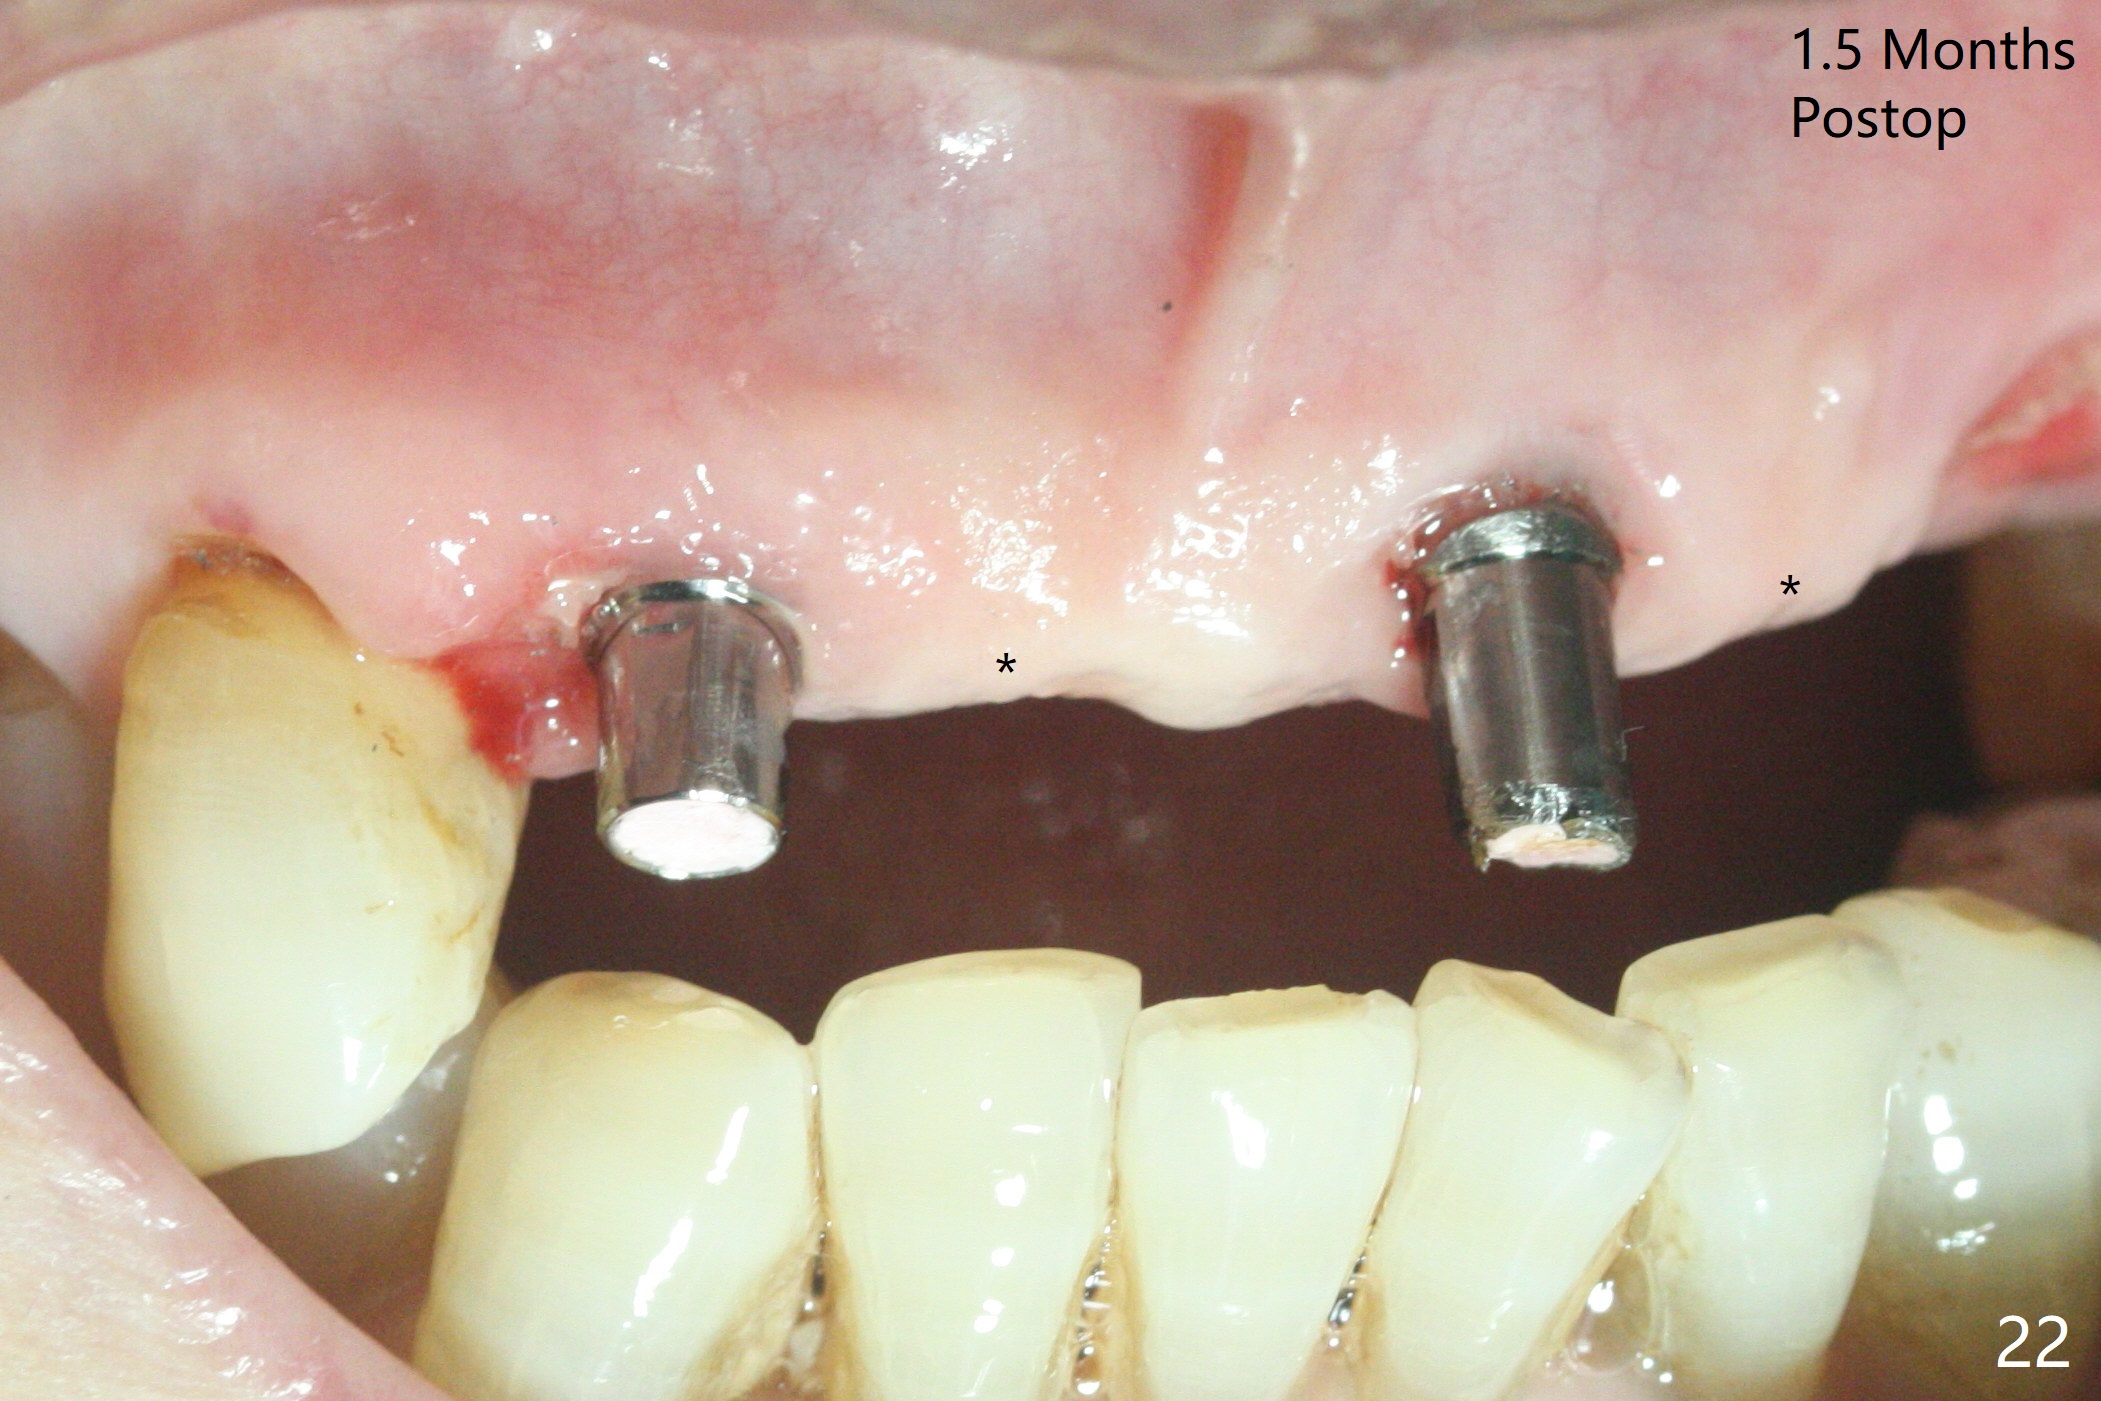

今天下午进入治疗室,粘性骨粉已制备:上清液来自红管(含促凝剂),离心3分钟(图一);再离心10分钟上清液就转变PRF,压制后,使用前剪成三块(图二:黑线),其中两块punch一个洞(图二:圆圈),插入7,9号牙基台固定;大块覆盖11/12号牙牙槽窝(图十四)。7,9,11,12号牙必须拔除(图三),然后在7,9,12种植。由于缺失左下磨牙,前牙垂直距离减少(图四)。完成9号牙位钻洞后,利用fixture mount(图五:M)植入植体,并留在原位固定导板(图六),然后7号牙种植,也留下fixture mount(图六:7,9),最后完成12号牙植入,但是后者扭力低,放置愈合螺帽(图九),而7,9号牙位放置修复基台(图七,八(使用5.5毫米profile drill后),好像基台没有完全就位。7号牙位更换基台似乎没帮助(图十),9号牙位再次放置同一个基台临床上仿佛有改变(比较图八与十二)。放置粘性骨粉后(图十一至十三),牙槽窝口覆盖PRF膜(图十四:P(A:基台)),最后使用树脂敷料固定骨粉和膜(图十五,六),基台帮助敷料固位,没有咬合干扰(图十七:*)。树脂敷料部分解决美观问题,一个月后撤除,如果植体仍有稳定性,可能制作7-10临时牙桥,可能部分维持或者恢复牙龈外形。术后一周病人主诉后面植牙和鼻底疼痛,11号牙根尖牙龈充血(图十八),轻度触痛,可能与术中尚未完全清创有关(图十九(术前CT 3D图像))。再服用Amoxicillin一周,症状好转,鼻底轻度触痛(图二十)。术后1.5月没有任何不适,撤除树脂敷料,7号牙基台(袖)显得太长,换一个短的(4.5x4(5)(图十,十一)->4x4(3)毫米)毫米),植骨好像愈合正常(图二十一:*)。7号牙换了短的基台,9号牙基台高度调整后,与对合牙有足够空间做临时牙桥,最好8,10号牙位牙龈应该凹陷(图二十二:*),有pontic外形。另外9号牙基台颊侧牙龈边缘有所修整,临时牙桥准备。先做7-10临时牙桥,理想临时牙桥pontic处树脂应该多些(图二十三:白线)压迫牙龈形成凹陷。11,12号牙牙槽窝在树脂(Bosworth)敷料下也正常愈合(图二十四)。